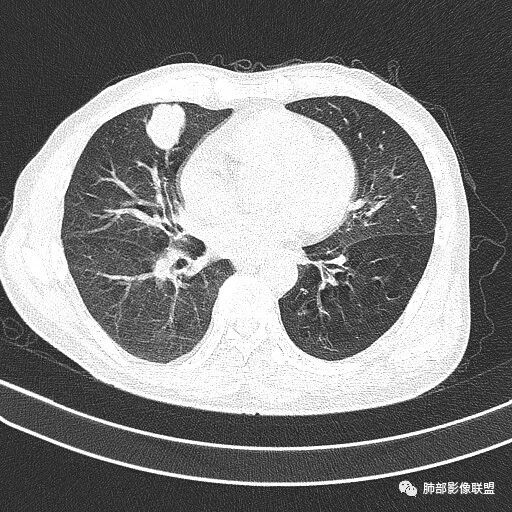

薇:各位老师,下面是该病例的横断位薄层

晨读病例  患者老年男性,因腰腹部疼痛3周,排尿困难1周入院。查尿常规及C反应蛋白提示泌尿系感染。肿瘤标志物NSE、细胞角蛋白19片断稍升高。胸部CT:右肺中叶内侧段类圆形肿块影,浅分叶,部分层面见深分叶,胸膜牵拉及支气管截断征象,边界清,密度低,无强化,且垮叶裂。综合考虑恶性病变,类癌及小细胞可能性大,鉴别囊肿等良性病变肺囊肿。

1.右肺中叶孤立不规则块影,浅分叶,未见液化或钙化,未见毛刺,未见脐凹,未见明显胸膜牵拉。

2.近肺门侧隐约见支气管截止。

3.外侧可见血管进入,病灶局部轻度强化。

上述均不符合光滑类圆形的支气管肺囊肿,也不符合典型的类癌,切不可先入为主。也不符合转移瘤。

4.肺门纵隔未见增大淋巴结。如此体量的肺块,没有增大淋巴结,不符合小细胞肺癌的生物学行为。

5.未见卫星灶,未见支气管增厚,结核也缺少支持点。

综上,应当鉴别的主要为肺鳞癌及结核灶